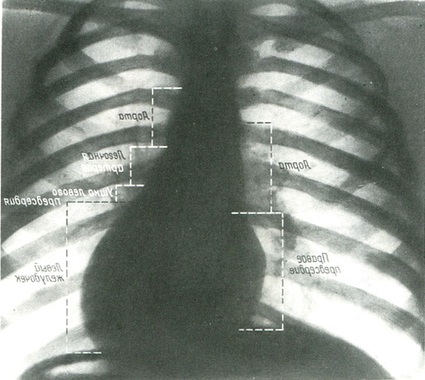

Передній знімок серця і великих судин роблять в строго симетричному положенні правої і лівої половин грудної клітки (рис. 377). Оцінюється і конституція людини, висота купола діафрагми. При високому або низькому стоянні діафрагми довга вісь серця змінює положення. На рентгенограмі 1/3 його тіні лежить праворуч від серединної лінії або на 2 - 3 см від краю тіні хребта, а 2/3 - зліва, у формі овального тіла з розширенням внизу. Зліва між тінню серця і судинами вимальовується «талія» серця. «Талія» добре видна при горизонтальному положенні і відсутня при вертикальному положенні серця. Контури аорти і легеневого стовбура завжди чіткі, рівні, мають форму дуг. Посилення малюнка цих дуг свідчить про гіпертрофії того чи іншого освіти серця.

377. Передній оглядовий знімок серця і великих судин грудної порожнини з позначенням дуг, що складають контури серця і судин (по Л. Д. Линденбратену).